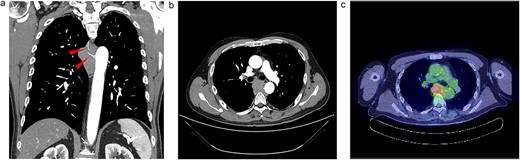

Upon examination for pneumonia during treatment for cerebellar infarction, a 53-year-old man was diagnosed with a posterior mediastinal tumour. He had a history of dyslipidaemia and had received appropriate medical treatment. Although the cerebellar infarction and pneumonia were in remission, the posterior mediastinal tumour persisted. He exhibited no systemic symptoms, and no abnormal physical findings were detected during a whole-body medical examination. Contrast-enhanced computed tomography (CT) revealed a 7-cm soft tissue shadow in the posterior mediastinum with clear and uniformly contrasted borders. There was no invasion into the adjacent vertebral body, and the blood vessels penetrating the interior were intact (Fig. 1a and b; red arrow). Positron emission tomography-CT (PET-CT) indicated a high maximum standardized uptake of 10.35 in the tumour, with no involvement of other lymph nodes or organs detected via whole-body imaging (Fig. 1c). Serum levels of various markers [including carcinoembryonic antigen, cytokeratin 19 fragments, beta-human chorionic gonadotropin, alpha-fetoprotein, soluble interleukin-2 receptor, immunoglobulin G, and serum C-reactive protein (CRP)] were within normal reference ranges. Endosonographic tissue confirmation via endobronchial ultrasound-guided transbronchial needle aspiration was inconclusive. Subsequently, thoracoscopic surgery was performed to obtain a biopsy for definitive diagnosis and treatment planning. The procedure, conducted using a complete thoracoscopic approach with three ports (7, 7, and 10 mm), revealed a solid hypertrophic lesion in the posterior mediastinum. A biopsy at two locations confirmed homogeneous, elastic, and soft tumours. The total operative time was 70 min with a bleeding volume of 30 ml. The patient experienced no postoperative complications and was discharged 7 days post-surgery. Postoperative histological analysis revealed a widespread collection of eosinophilic histiocytes, lymphocytes, and plasma cells (Fig. 2a). Immunohistochemical examination indicated positivity for S-100 protein, oct-2, and cyclin D1 (Fig. 2b–d), with an approximate IgG4-positive to IgG-positive plasma cell ratio of 24.7%. Consequently, the patient was diagnosed with RDD. The patient remains asymptomatic, is currently under outpatient monitoring without treatment, and showed no exacerbation of his condition up to 6 months post-surgery.

Radiologic findings. (a) A 15-cm soft tissue shadow in the posterior mediastinum of Th6-10, presenting as a multinodular mass. (b) Thoracic paravertebral soft tissue mass in the axial view. (c) Image of positron emission tomography-CT.